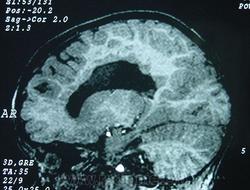

Гетеротопии. Перивентрикулярная гетеротопия. Субэпендимальная нодулярная (узелковая) гетеротопия.

Наиболее частым вариантом миграционных нарушений является гетеротопия - скопление нейронов, остановившихся в различных аномальных местах на пути следования к коре головного мозга. Такая остановка происходит не позже 5-го месяца внутриутробного развития. Изолированный участок узловатой массы называется «гетеротопион». В настоящее время описаны следующие варианты гетеротопии:

- субэпендимальная нодулярная (узелковая) гетеротопия;

Перивентрикулярная субэпендимальная гетеротопия